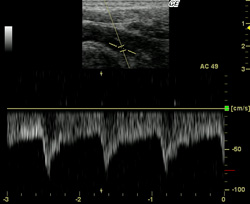

頸動脈エコーとは

頸動脈エコー(頸動脈超音波検査)とは、超音波によって血管内腔の形状や血管内膜面および血管壁の状態を調べる検査です。近年、脳梗塞や一過性脳虚血発作の原因として挙げられている頸部血管の動脈硬化も、頸動脈への超音波検査によって早期発見が可能です。動脈硬化はメタボリックシンドロームからも引き起こされるとされ、近年のメタボリックシンドローム患者の増加から、今後頸動脈エコーの需要は増えていくことが予想されます。

頸動脈エコーでわかる病気

脳梗塞

心筋梗塞

狭心症 etc・・・